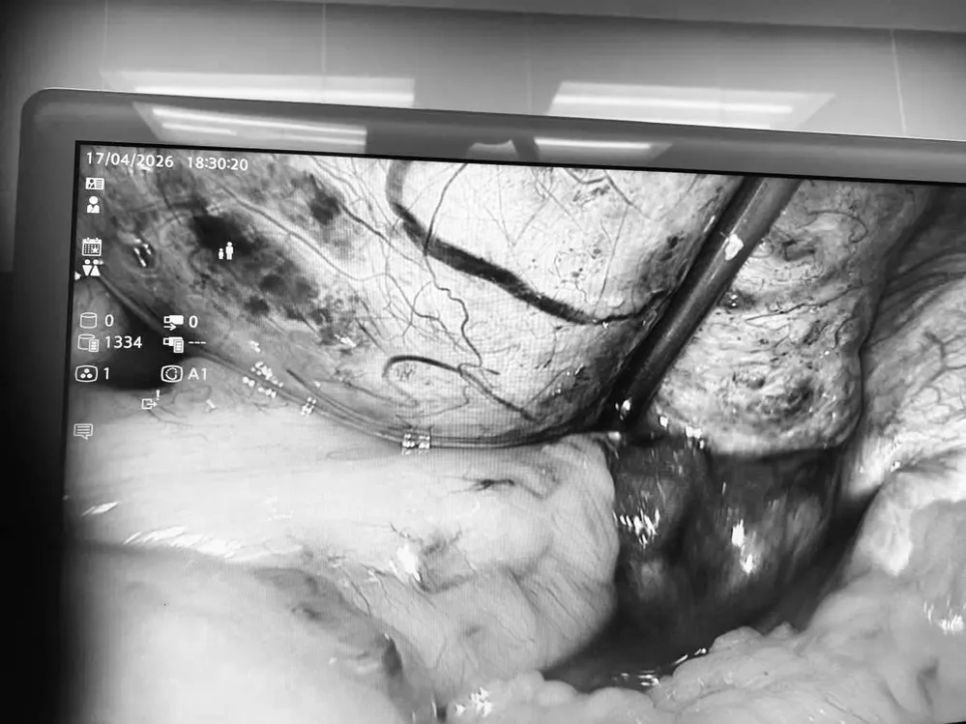

Trong quá trình nội soi, các bác sĩ ghi nhận khối u nang lớn cạnh buồng trứng phải, kéo theo tai vòi và buồng trứng xoắn đến 5 vòng, chuyển màu tím đen do thiếu máu nuôi.

Ê-kíp phẫu thuật đã tiến hành tháo xoắn, cắt bỏ u nang dạng bì. Sau can thiệp, buồng trứng và tai vòi hồi phục màu hồng và được bảo tồn hoàn toàn nhờ xử trí kịp thời.